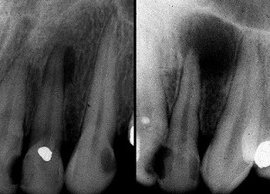

Образование растет медленно и на первых порах не проявляет себя каким-либо образом. Наиболее простой способ обнаружить кисту – сделать рентгенографию челюсти, в результате на снимке будет видно темное затемнение с четко выраженными краями. Проблему следует ликвидировать, иначе начнется разрушение кости или серьезное инфицирование. В случае если защитные свойства иммунитета падают, и организм находится в подавленном состоянии, киста начинает активно развиваться.

Единственным надежным способом диагностики — рентгенография. Очень часто бывает, что кисту обнаруживают случайно, делая рентгенограмму и обнаруживая новообразование.

Как выглядит киста на снимке

Как уже было сказано, единственным надежным методом диагностики кисты является рентгенографическое исследование. На снимке она выглядит как темное округлое или овальное пятно, которое четко очерчено. Обычно расположена у верхушки корня зуба. Ошибиться с диагнозом просто невозможно, даже начинающий врач-стоматолог легко сможет распознать болезнь на рентгене.

Единственное исключение представляет киста зуба, которую не видно на рентгене. Обычно так бывает, если не весь корень зуба попал в поле видимости рентгеновского снимка, и расположена частично за гранью снимка. В этом случае, если у врача возникают подозрения на наличие кисты или гранулемы, следует сделать повторный снимок, который бы полностью отобразил всю корневую систему подозрительного зуба, а также соседних.